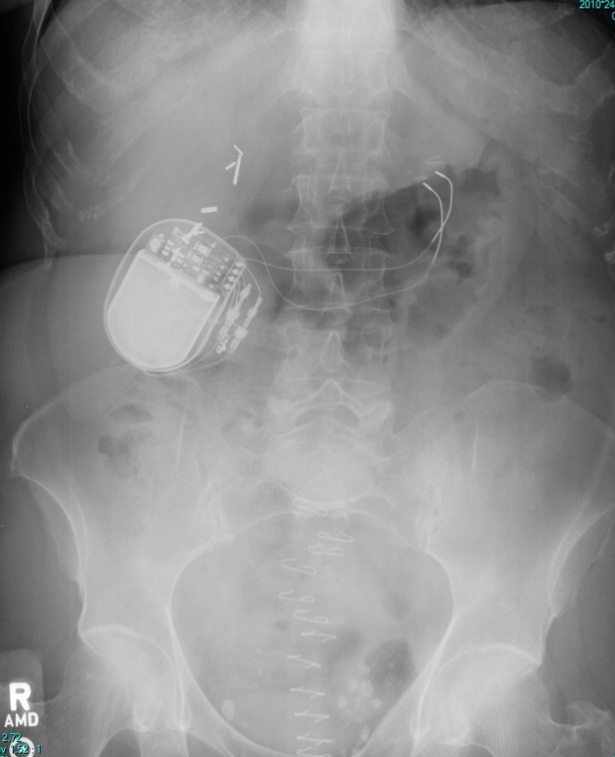

69 year old female.

KUB

Surgically implanted devices are commonly seen on X-Ray.  Being able to correctly identify is important.  For the film above, identify the following:

1.  What is the implanted device?

2.  What condition is this device used to treat?